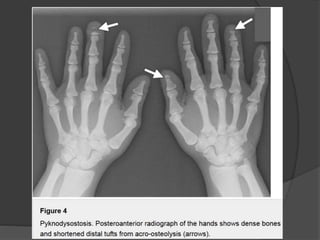

Patients with pyknodysostosis present with a complex of characteristic

features, including

• dwarfism

• pectus excavatum

• short fingers from acro-osteolysis

• hypoplasia of the facial bones, causing dysmorphic facial features.

Radiographically, there is generalized osteosclerosis similar to osteopetrosis,

but with preservation of the medullary canal of long bones.

Dense vertebral bodies with characteristic sparing of the transverse

processes is seen.